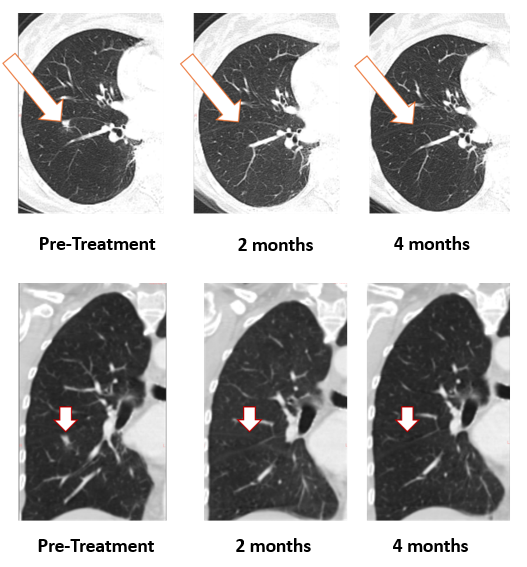

Figure 1: Treatment with Bria-OTS monotherapy resulted in 100% resolution of tumor in the lung of the metastatic breast cancer (MBC) patient following 2 months of therapy and confirmed at 4 months of therapy1 (axial and coronal views)

As shown, the lesion in the patient’s right lung is undetectable after two months and confirmed resolved at 4 months. The updated images supersede those previously reported.

1 Note that the other white dots in the lungs are blood vessels.